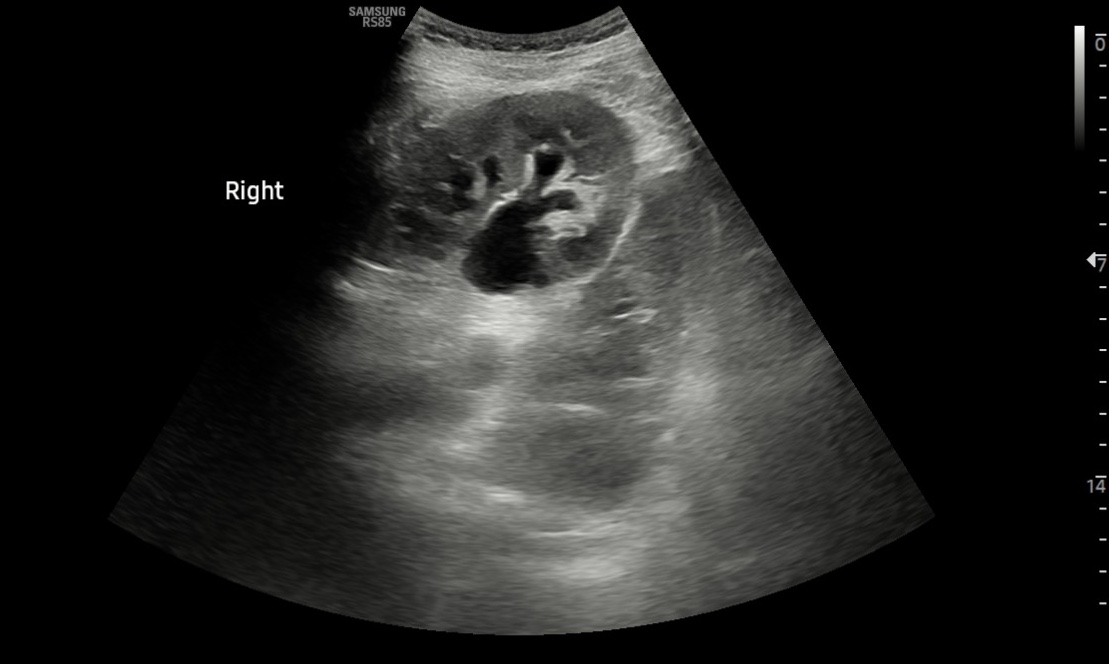

Hallazgos ecográficos

• Ambos riñones de tamaño y parénquima conservados. Objetivamos una hidronefrosis derecha grado 2. Parece apreciarse una imagen compatible con litiasis en uréter proximal y mínima cuña de líquido libre en polo inferior del riñón derecho.